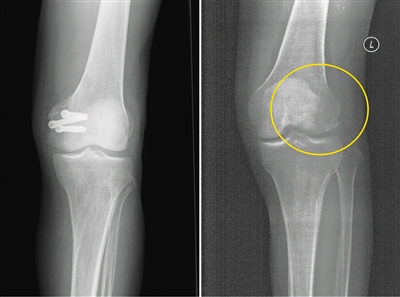

左為使用金屬螺釘后拍攝的影像,右為使用蠶絲螺釘后拍攝的影像。受訪者供圖

在長期的臨床應用過程中,金屬材料逐漸顯現出三大缺陷:一是金屬內固定往往需要二次手術取出,大大增加了患者的痛苦及經濟負擔。二是金屬的力學強度遠遠超過骨骼,導致應力遮擋,影響骨折愈合。此外,使用部分金屬材料術后無法進行CT和磁共振拍攝;即使鈦合金材料可以進行檢查,也存在明顯的偽影,螺釘周邊模糊一團,嚴重影響影像觀察的效果。

今年5月,患者張強(化名)不慎扭傷,造成左股骨遠端骨折。由于骨折部位靠近關節面,使用金屬螺釘固定時應力過大,會影響骨折愈合;1年后還需要手術將金屬螺釘取出,可能造成二次創傷。患者入院之后,團隊經過詳細探討病情、細致閱片后認為,該患者符合可降解蠶絲螺釘固定的適應證。術中團隊對該患者使用可降解蠶絲螺釘固定骨折塊,術后的CT片中沒有任何偽影,可以清晰地看到骨折塊已經完全復位,并且解除了患者二次手術取出螺釘的負擔和困擾。